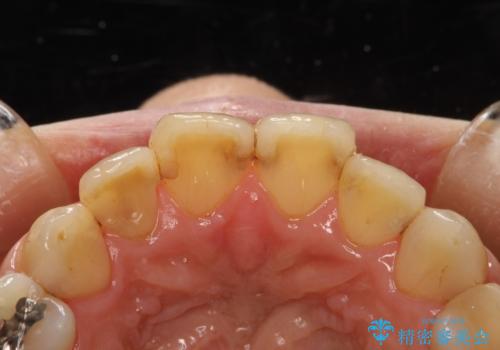

歯と歯の間の着色除去

- 着色が歯と歯の間や、詰め物との境目に多い患者様。

細かい部分まで届くようにエアフローにて施術しました。

詰め物との境目の汚れは、ポリッシングブラシでは取り除くことが難しいため

エアフローの細かいパウダーを角度を変えて当ててとれる範囲で除去しました。